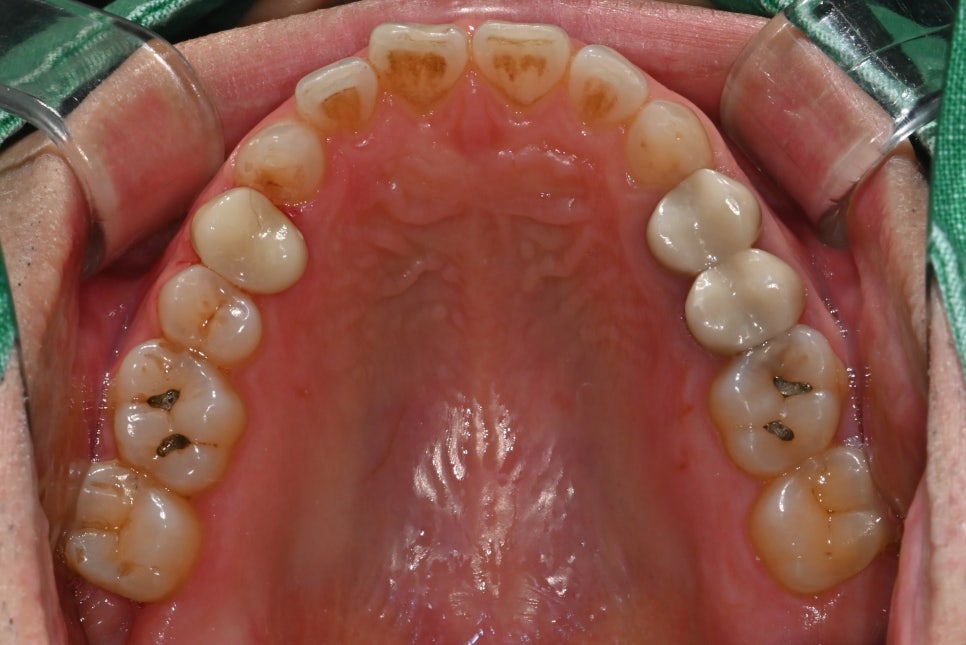

두 번째 사진: 초진 시 촬영한 상악(윗니) 어금니 사진입니다. 충치 부위와 깨진 치아 상태가 확인됩니다.